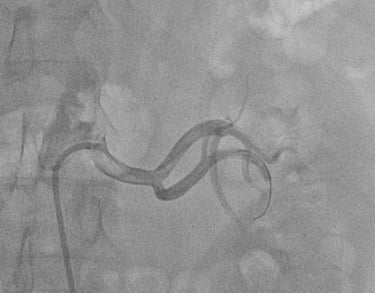

ANGIOPLASTICA

Angioplastica coronarica e lo stent

Si tratta del piu' comune trattamento attualmente utilizzato per curare l'aterosclerosi coronarica. E' una metodica che si avvale di molteplici strumenti appositamente ideati e realizzati e puo' essere effettuata subito dopo la coronarografia, utilizzando la stessa via di accesso arterioso. Solitamente, il paziente sottoposto ad angioplastica coronarica programmata puo' essere dimesso il giorno successivo alla procedura. Lo stent coronarico e' un dispositivo di grandezza millimetrica, in lega metallica biocompatibile (quindi senza fenomeni di rigetto), che viene utilizzato di solito dopo la dilatazione dell'arteria coronarica con il palloncino, per mantenere la pervietà della arteria.